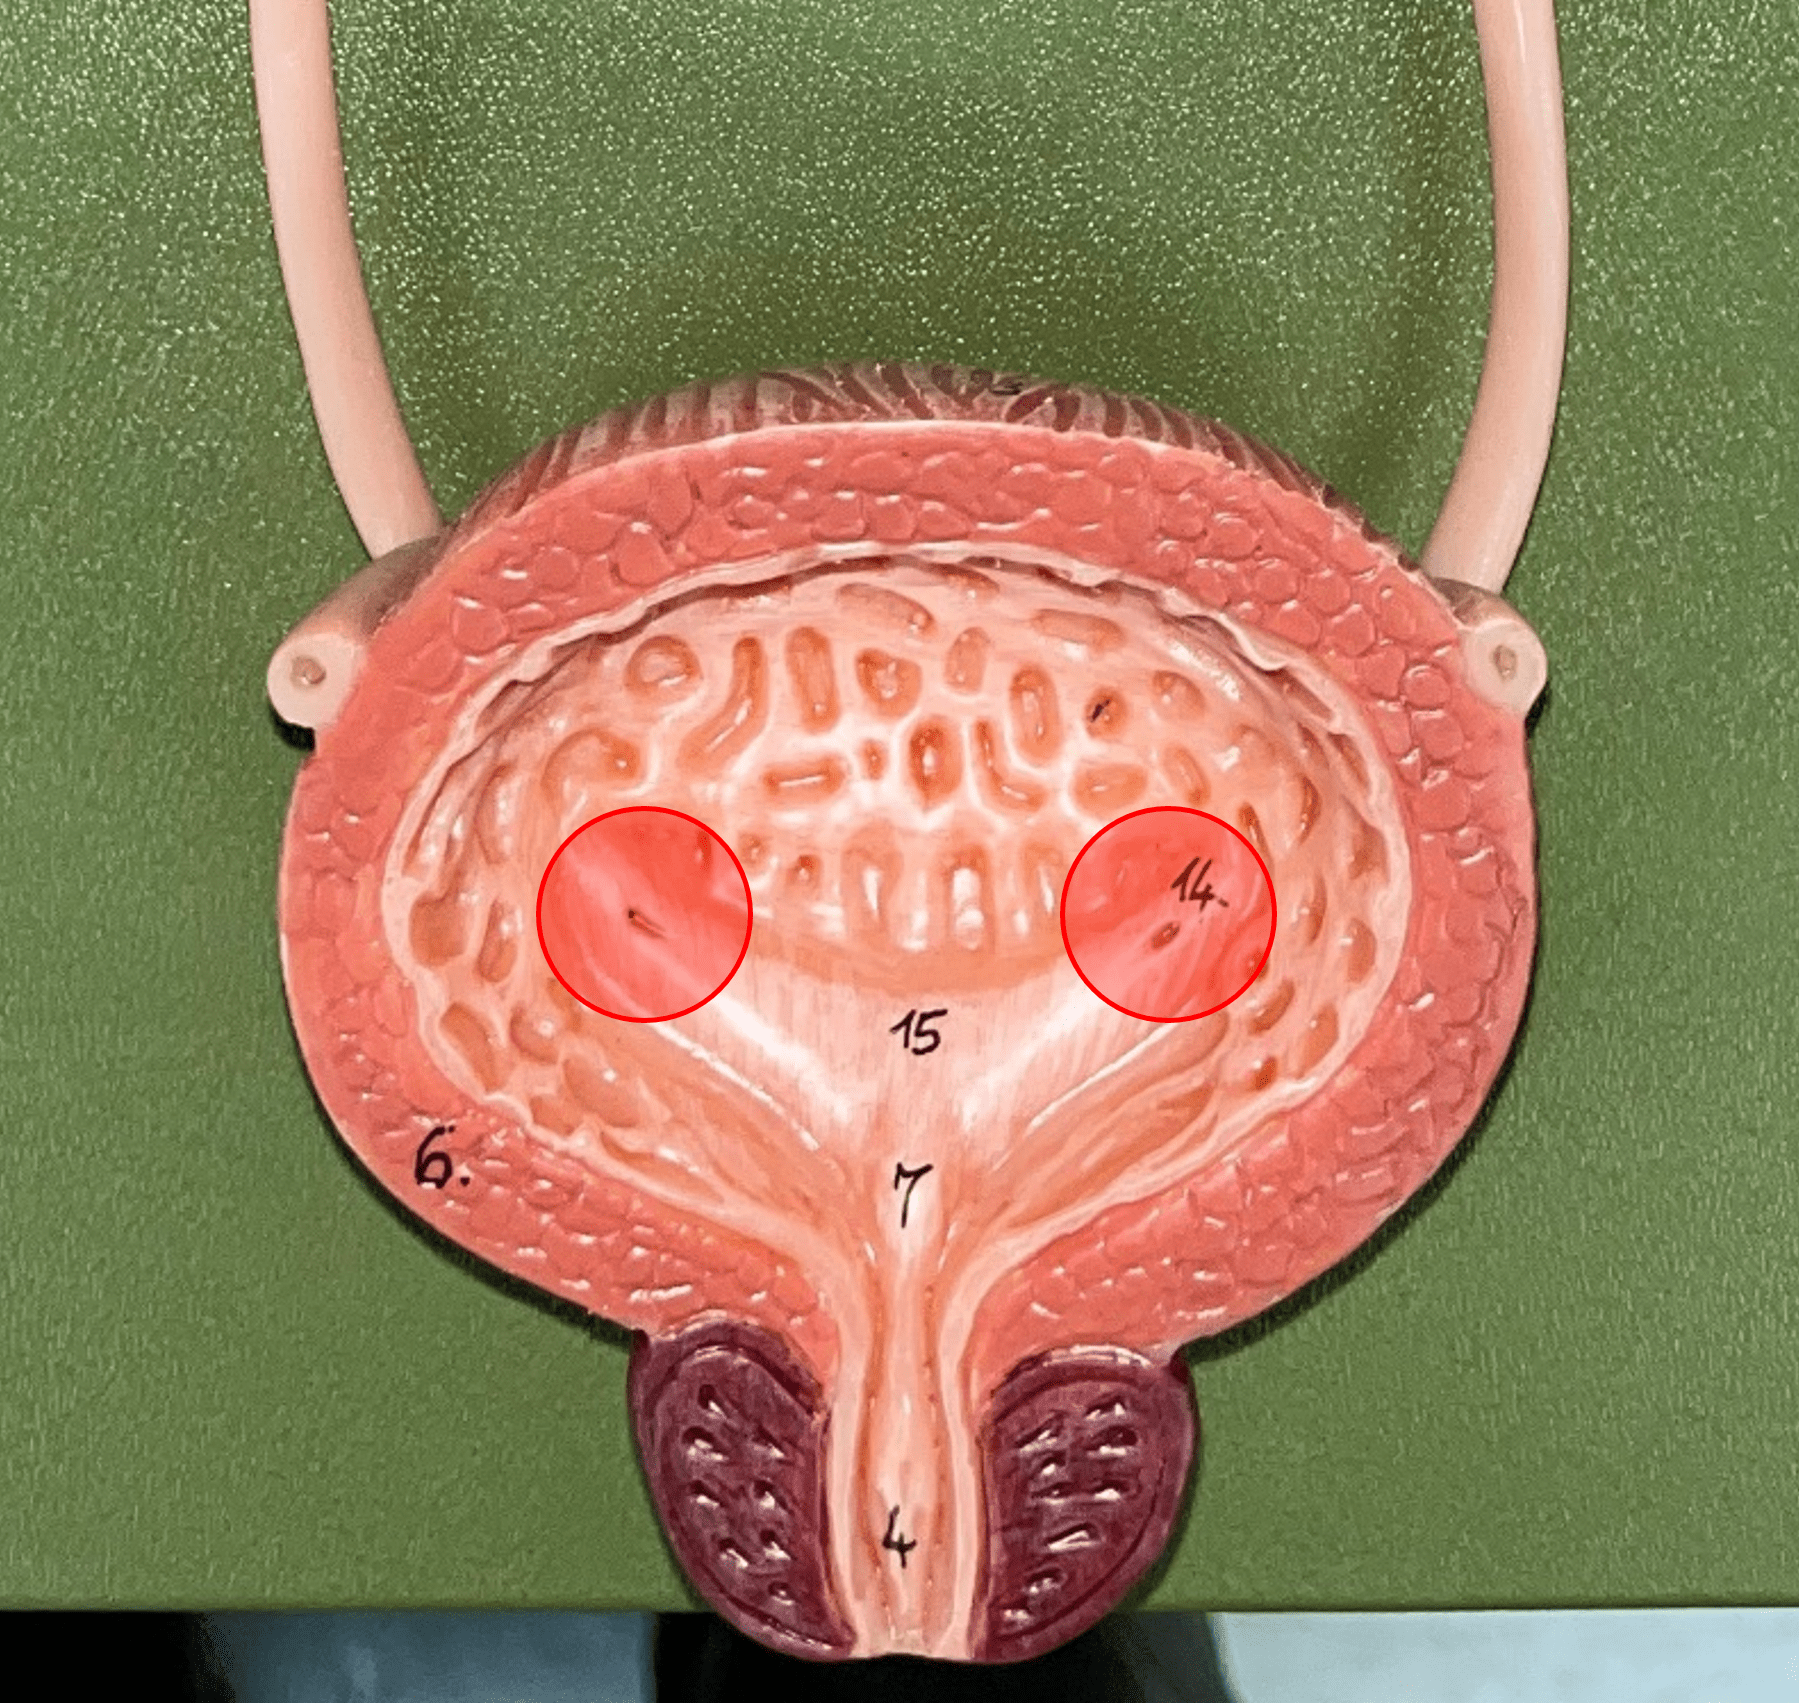

ureteral opening

• Part of the urinary bladder.

• A posterior opening on either side of the of the bladder led in by the ureters.

• A posterior opening on either side of the of the bladder led in by the ureters.